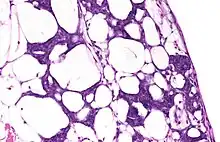

During the last century, blastemas were thought to be composed of undifferentiated pluripotent cells, but recent research indicates that in some organisms blastemas may retain memory of tissue origin.[3] They are typically found in the early stages of an organism's development such as in embryos, and in the regeneration of tissues, organs and bone.[4]

Some amphibians and certain species of fish and two species of African spiny mice can produce blastemas as adults.[5] For example, salamanders can regenerate many organs after their amputation, including their limbs, tail, retina and intestine.[6] Most animals, however, cannot produce blastemas.

As stated above, there are several different types of organisms that can utilize a regenerative blastema as an adult. These organisms include urodele amphibians, zebrafish, and planarian flatworms as major creatures of study. In flatworms, the formation of a blastema needs adult stem cells that are called neoblasts for any type of regeneration to occur.[11] Flatworms use these undifferentiated cells for regeneration after paracrine factors can provide signals from the surface of the wound. The cells in the blastema are also referred to as clonogenic neoblasts (cNeoblasts) that are able to move to the site of the wound and reform the tissue.[12] In urodele amphibians, studies suggest that dedifferentiation of cells leads to the formation of a blastema that is able to form multiple tissue types after the amputation of their tails and wound healing occurs.[13][14] In zebrafish, and in general, it seems as if experts are still uncertain of what truly forms the blastema. However, two common theories that have often been expressed are cell dedifferentiation and the recruitment of stem cells to the wound site.[15]